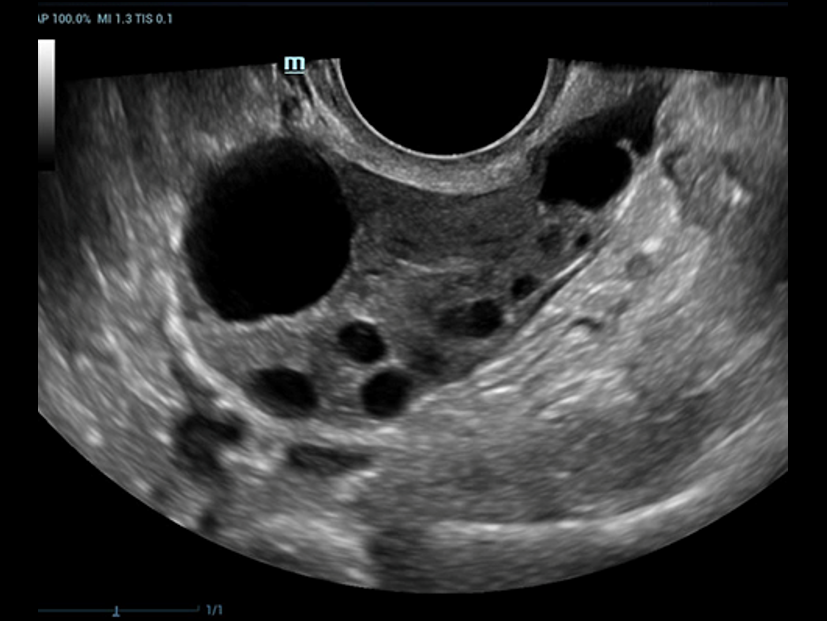

Desde que se fund├│ la compa?├Ła, Mindray ha explorado incansablemente nuevas formas de mejorar la confiabilidad del diagn├│stico. Con la revolucionaria tecnolog├Ła de ZONE Sonography?, la nueva plataforma ZST+ de Resona?7 lleva la calidad de la imagen por ecograf├Ła a un nivel superior mediante el procesamiento de datos de canal y la adquisici├│n de zona.

Adem├Īs de la calidad de imagen de primer nivel, Resona?7 tambi├®n mejora las capacidades de investigaci├│n cl├Łnica con el revolucionario V?Flow para la evaluaci├│n hemodin├Īmica vascular y con la adquisici├│n de planos m├Īs inteligente a partir de conjuntos de datos 3D para el diagn├│stico del SNC fetal. Al combinar el funcionamiento multit├Īctil basado en gestos m├Īs intuitivo y todas las caracter├Łsticas cl├Łnicas esenciales, Resona?7 realmente lidera las novedades en innovaci├│n de ecograf├Łas.